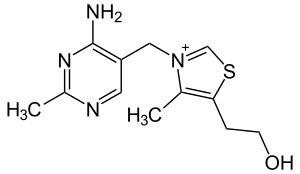

| Thiamine | |

| Causes | Thiamine deficiency (vitamin B1)[2] |

It occurs due to deficiency of thiamine (vitamin B1), often due to alcoholism, though other causes may also result in the condition.[2][3] The underlying mechanism involves damage to cells in the brain and spinal cord.[2] It is part of a spectrum of disease known as Wernicke–Korsakoff syndrome, together with Wernicke encephalopathy.[2] Diagnosis is based on symptoms after ruling out other causes.[3]

Thiamine is essential for the decarboxylation of pyruvate, and deficiency during this metabolic process is thought to cause damage to the medial thalamus and mammillary bodies of the posterior hypothalamus, as well as generalized cerebral atrophy.[10] These brain regions are all parts of the limbic system, which is heavily involved in emotion and memory.

Conditions resulting in thiamine deficiency and its effects include chronic alcoholism and severe malnutrition.[19] Alcoholism may co-occur with poor nutrition, which in addition to inflammation of the stomach lining, causes thiamine deficiency.[20] Other causes include dietary deficiencies, prolonged vomiting, eating disorders, and the effects of chemotherapy. It can also occur in pregnant women who have a form of extreme morning sickness known as hyperemesis gravidarum.[21] Mercury poisoning can also lead to Korsakoff syndrome.[22] Though it does not always co-occur, this disorder can emerge frequently as a consequential result of Wernicke's encephalopathy.[23]

The most effective method of preventing AKS is to avoid thiamine deficiency. In Western nations, the most common causes of such a deficiency are alcoholism and eating disorders.[25] Because these are behavioral-induced causes, Korsakoff syndrome is essentially considered a preventable disease. Thus, fortifying foods with thiamine, or requiring companies that sell alcoholic beverages to supplement them with B vitamins in general or thiamine in particular, could avert many cases.[27][28]

It was once assumed that anyone suffering from KS would eventually need full-time care. This is still often the case, but rehabilitation can help regain some, albeit often limited, level of independence.[25] Treatment involves the replacement or supplementation of thiamine by intravenous or intramuscular injection, together with proper nutrition and hydration. However, the amnesia and brain damage caused by the disease does not always respond to thiamine replacement therapy. In some cases, drug therapy is recommended. Treatment typically requires taking thiamine orally for 3 to 12 months, though only about 20 percent of cases are reversible. If treatment is successful, improvement will become apparent within two years, although recovery is slow and often incomplete.

As an immediate form of treatment, a pairing of intravenous or intramuscular thiamine with a high concentration of B-complex vitamins can be administered three times daily for 2–3 days. In most cases, an effective response will be observed. A single dose of 1 gram of thiamine can also be administered to achieve a clinical response.[29] In those who are seriously malnourished, the sudden availability of glucose without proper bodily levels of thiamine to metabolize is thought to cause damage to cells. Thus, the administration of thiamine along with an intravenous form of glucose is often good practice.[30]